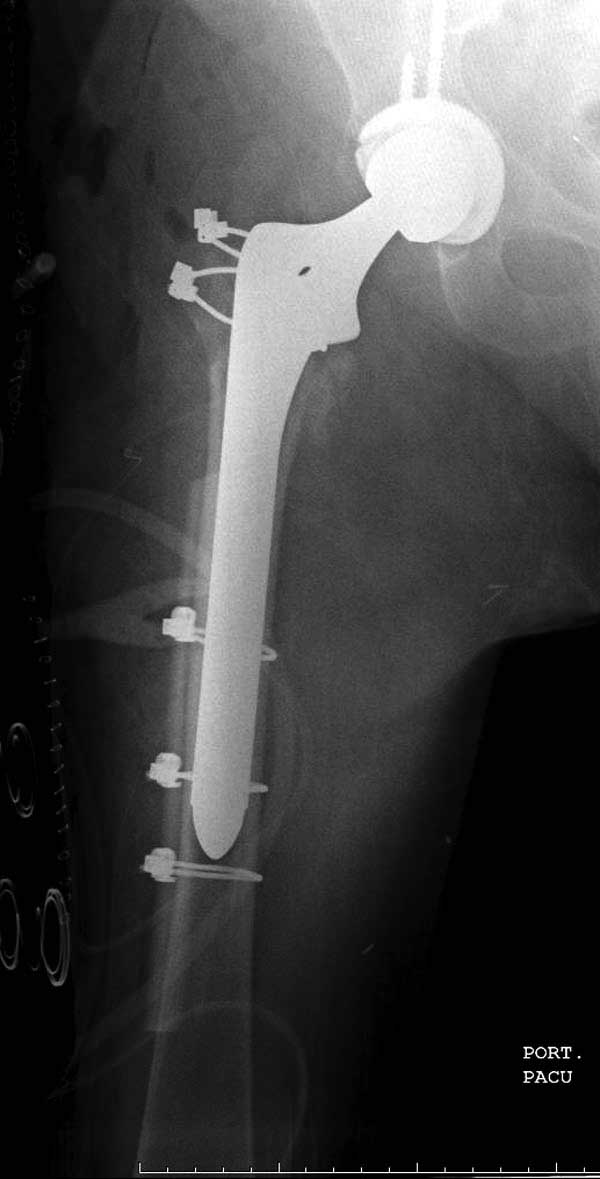

Банальный рутинный перелом чрезвертельной зоны лечимый DHS.

А по картинке можно сказать, что вроде бы все и неплохо. Предупредить миграцию шеечного винта при наружной ротации диафиза во время ходьбы достигают введением последнего поближе к переднему кортексу шейки. На Вашей картинке винт "смотрит" кзади. Отсутствие дополнительной боковой опоры для винта создает предпосылки для несостоятельности фиксации. (См. статью в прикреплении). Поэтому с ранней активизацией пациента в данном случае я бы подождал.

При таком переломе мы бы тоже поставили вертельный гвоздь - на следующий день встать и побежать - чем не перспектива? На прямом снимке винт стоит замечательно, а коварный аксиальный подкачал, хотелось бы больше по центру шейки и головки завести. Да и смещение, какое-никакое, но есть. Посему - нагрузка 15 кг, а расширяли бы не раньше, чем через 5 недель.

Что касается данного перелома, то по-моему DHS или гамма - принципиальной разницы здесь конкретно нет - медиальная опора сохранена, при правильном исполнении можно ногу нагружать. Технически здесь выполнено на 3+, но если так же винт гаммы поставить - лучше не было бы.

Прилагаю снимок сделанный еще в стационаре через 2 недели после операции.

Да, согласен, в такой же репозиции Гамма был бы таким же несостоятельным фиксатором. Проблема в репозиции медиального кортекса, который судя по снимку на месте и опора есть, а на самом деле не так. Как можно его проконтролировать? Дигитально, указательным пальцем пробраться через рану и пощупать? Иногда можно так репонировать перелом шурупом DHS - щупать пальцем язык перелома, который часто около малого вертела и можно до него достать пальцем и при малом разрезе, и поворачивая шуруп еще закручивая его на рукоятке репонировать перелом когда шуруп начнет брать кость. Если остеопороз не сильный и шуруп берет сразу, можно поставить антиротационный шуруп при репонированном положении перелома.

Проблема основная тут в остаточном варусе. Даже если отломки по медиальной стенке при этом окажутся в контакте, от cutout это не спасет. Плюс короткий винт, еще и эксцентрично расположенный, так что совсем мало кости ему резать надо.

Сеньоры-пэры ревизировали гвоздем, шуруп поставили по той же дорожке, только поглубже. Да еще и bone graft не пожалели. "Результат" уже был через 2 дня.

Если сохранять головку - думаю надо было в валгусе фиксировать перелом гвоздем, или DCS, т.к. все-равно разрезали, чтоб достать DHS.

Первые снимки показывают технические погрешности установки DHS. Не была достигнута репозиция, конечность в флексии и шейка в ротации. Сегодня все меньше обращают внимание на параметры для оценки репозиции (S контуры Lowell в обеих проекциях и Garden Alignment Index, в норме 155 и 180 градусов), хотя такие простые тесты помогли бы дорепонировать смещение. Винт находится сзади в головке, что при нагрузке поменяет вектор и вместо компрессии в линии перелома срежет головку-Cut Out!

В зависимости от дистанции линии перелома и латерального кортекса надо использовать разной длины barrel, т.е. конец баррели не должен доходить до пределов перелома. Здесь конец длинного ствола упирается в медиальный фрагмент, что мешает созданию компрессии, а более короткий barrel создал бы запас для компрессии. В боковой пластине вместо 4х можно было ограничится двумя шурупами, потому что головка шурупа в 4.5 мм выдерживает давление до 350 кг.

Вторая операция- это фаза сохранения головки бедра. Желательно приложить все усилия и сохранить головку, но, как видно, “фиаско” продолжается. Здесь вместо нейтрализации сил между медиальной и латеральными сторонами была попытка удержать варус. Варус не удержать ни деротационными шурупами о котором говорили и не костными стружками вбитые в шейку, потому что вся нагрузка упирается в головку.

Третья операция-продолжения усилии “синьорами пэрами” по разрушению нормальной анатомии. Крест на головку! По видимому возраст позволяет биполярную конструкции, и при дефекте calcar пошли на обычный цементный. Ягодичные мышцы потеряли связь с вертелом, т.е. отсутствует верхний удержатель, и результат “a Big Screw Up!” Снимки вызывают головокружение!